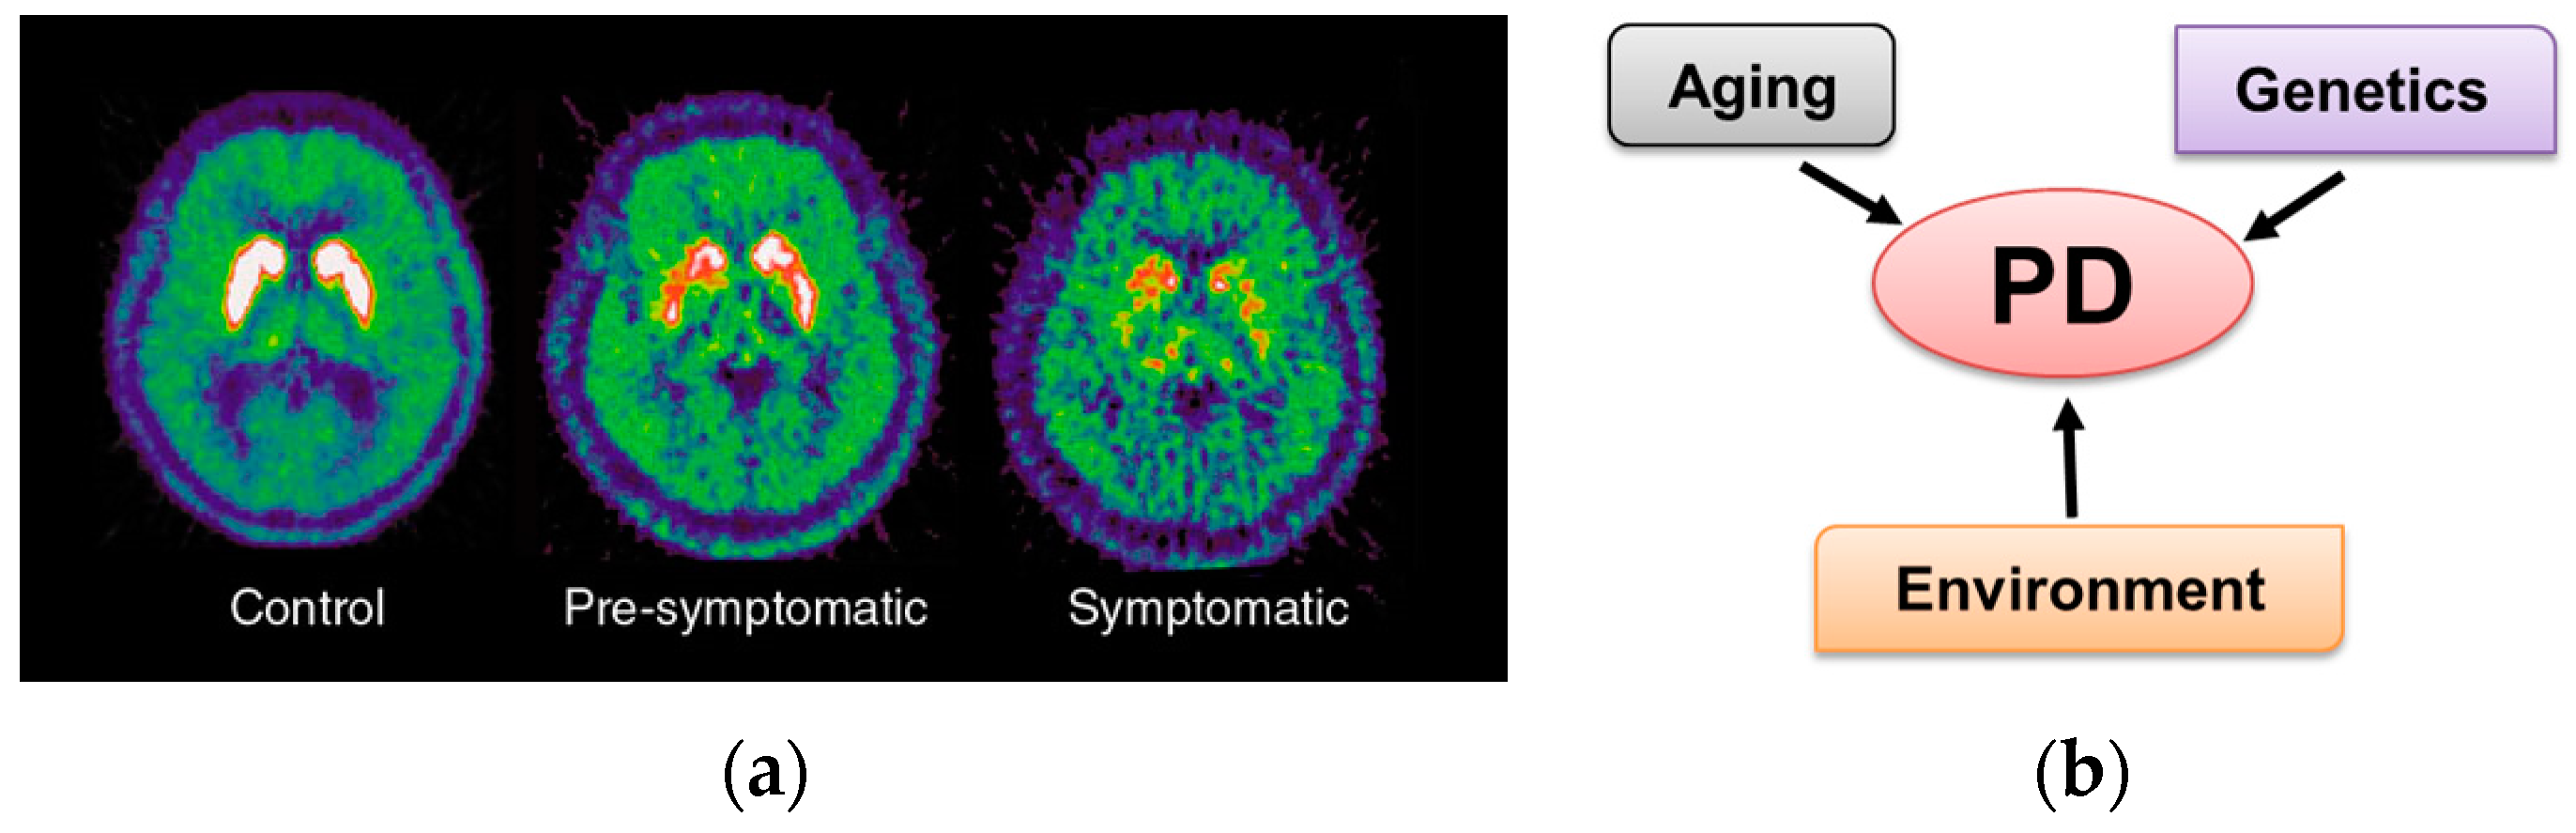

1.1. Parkinson’s Disease Overview